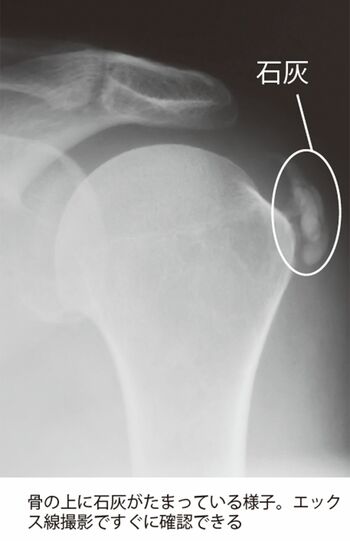

骨の上に石灰がたまっている様子。エックス線撮影ですぐに確認できる

[写真 2/5枚目] 骨の上に石灰がたまっている様子。エックス線撮影ですぐに確認できる